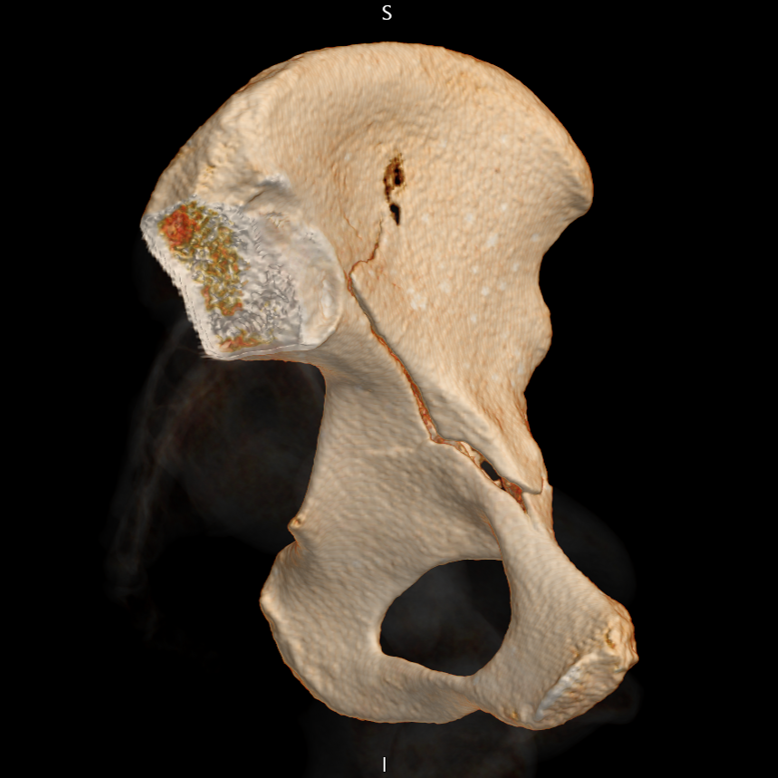

Thank you ESGAR for the Magna Cum Laude award of this #Esgar2023. This award is not only mine but also from my colleagues Dra.Canales, Dra. Garcia Latorre and nicolas almeida and great collaboration of Gopal Punjabi